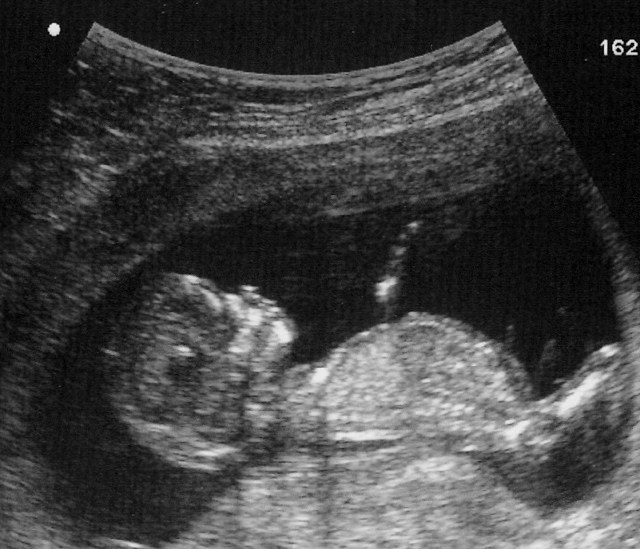

Birth Injury Cases Require Much Detail in Developing a Case

The imminent delay in recognizing that the baby was suffering...